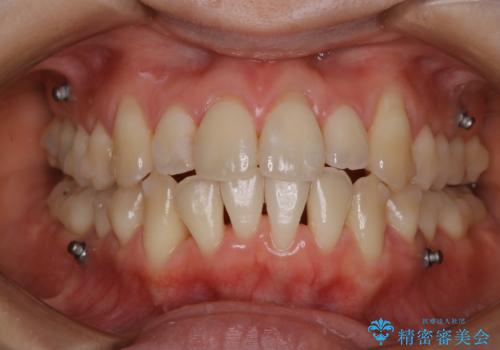

インビザライン中の方 結婚式前にPMTCでステインの除去

- インビザラインでの矯正治療中ですが、結婚式があるため全体の着色・ステインを綺麗にしたいとのことでした。PMTC60分コースを行いました。

PMTC(保険外治療)は、毎日の歯磨きで落としきれない汚れや、コーヒ、紅茶・タバコのヤニなどの着色も除去します。目には見えない歯と歯の間・歯肉の境目・インビザライン中はアタッチメント周囲などに残っているプラーク(歯垢)もしっかり取り除きます。PMTCでは専門的な機械や材料を使用して、徹底的に汚れを除去するため、虫歯・歯周病・口臭予防などにつながります。

またPMTCを行うことで、ご自身本来の歯の色になり自然な明るさになります。

口元が自然な明るさになることで、より清潔感のある印象になるため結婚式・行事やイベント前などにもPMTCを行うはおすすめです。